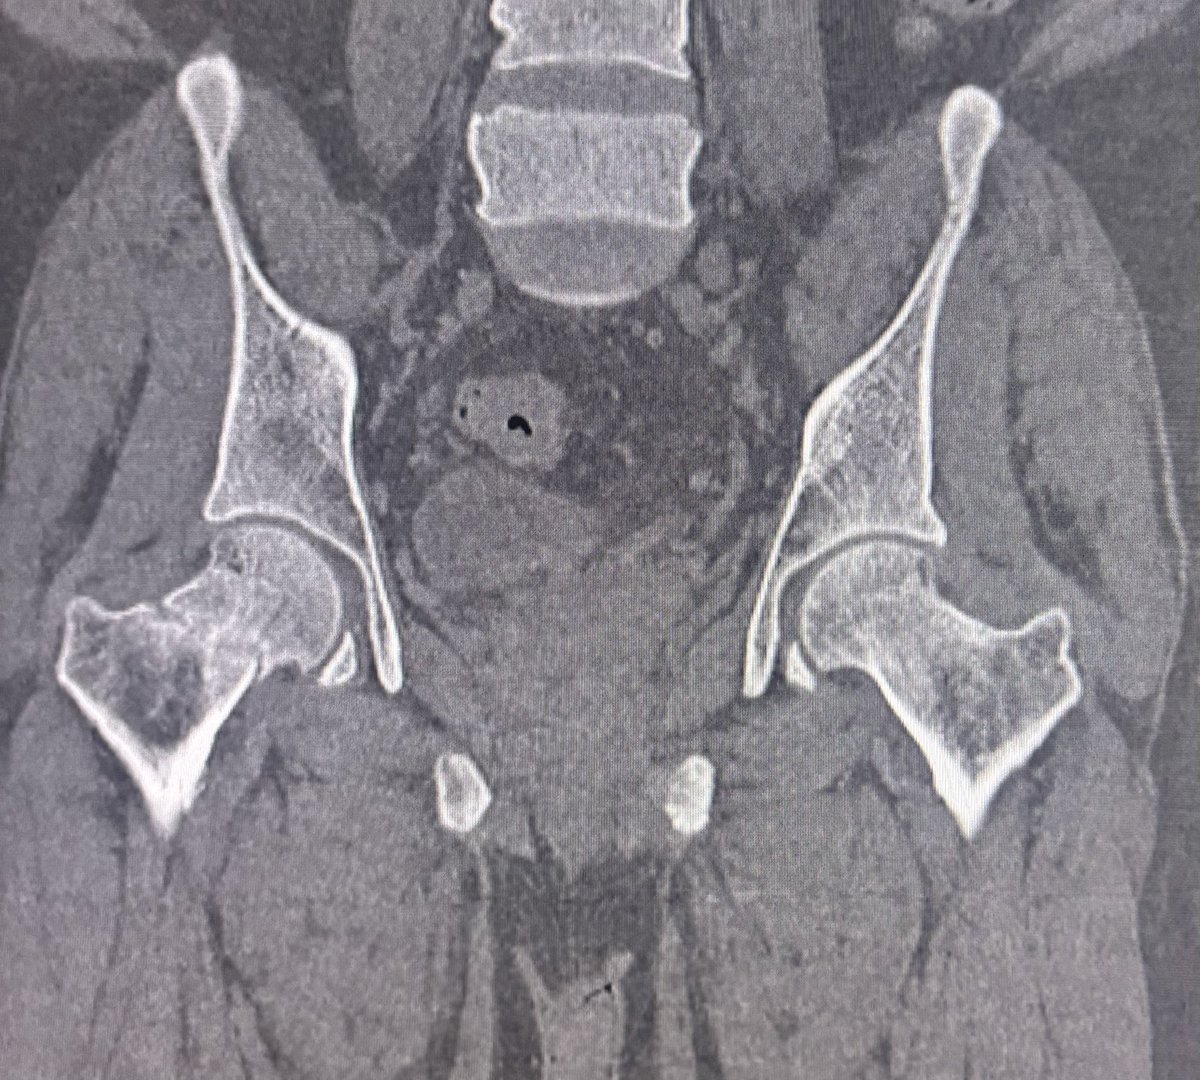

36 year old male with hip pain since 20 days.

What is the most likely diagnosis?

#Orthotwitter

#MSKradiology